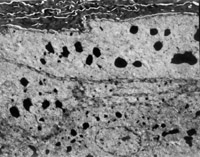

经MEBT/MEBO治疗20天,电镜观察到基底细胞层与纤维母细胞之间的半桥粒连接,同时可见纤维母细胞内粗面内质网结构和线粒体增生活跃(图5-3-19~5-3-21)。 MEBT/MEBO治疗30天后,上皮组织再生修复,已基本完成,创面组织切片显示胶原纤维成熟,排列整齐(图5-3-22),直径为0.1~0.5祄,并可见明暗相间周期性横纹(64nm),未见到胶原纤维扭曲和呈旋涡、菜花等病理形态。

5-3-20 粗面内质网结构和线粒体增生活跃 TEM×17000

5-3-21 同上 TEM×20000

5-3-22 MEBT/MEBO治疗30天,整齐排列的胶原纤维,纤维均匀一致直 径 0.1~0.5祄,有明暗相间的周期性横纹(64nm)